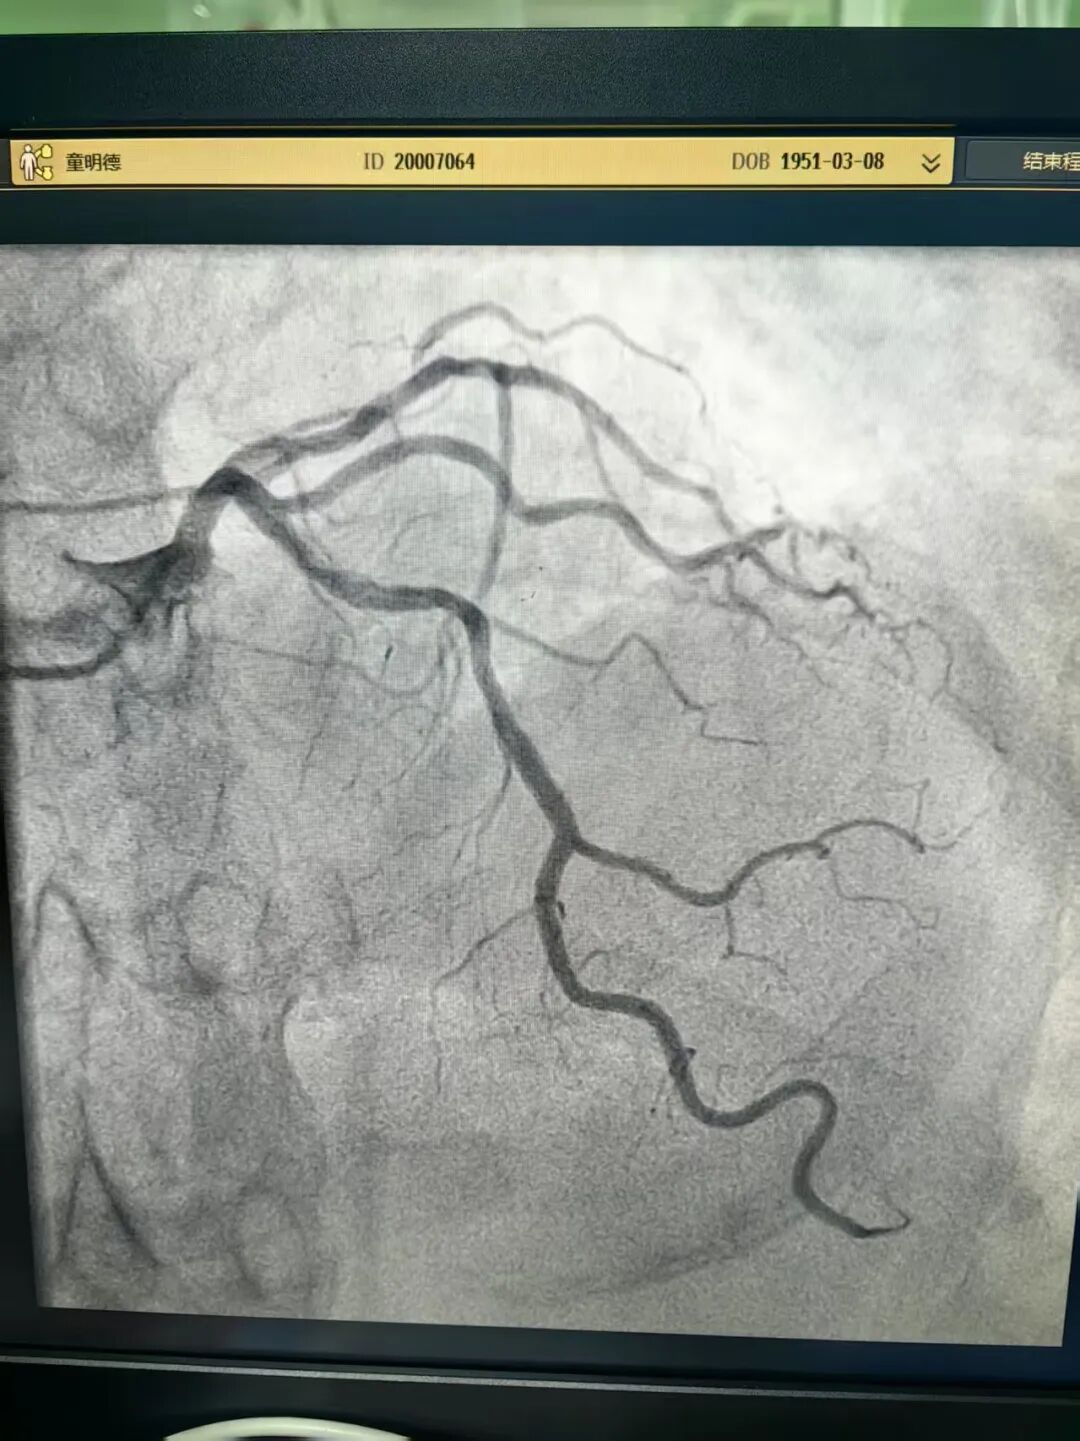

此外,一名74岁的男性患者因PCI(经皮冠脉介入术)术后17年再发胸痛前来就诊。冠脉造影显示他前降支近端模糊病变,肉眼判定其狭窄程度并不严重,但患者症状典型。

林茂欢副主任医师带领团队使用IVUS(血管内超声)技术辅助诊断,证实该处管腔面积明显狭窄,最终为他精准植入两枚支架。术后,患者管腔面积显著增加,症状完全缓解。这一手术的成功实施,标志着花都院区冠脉精准介入诊治迈入了新的阶段。

术后照片